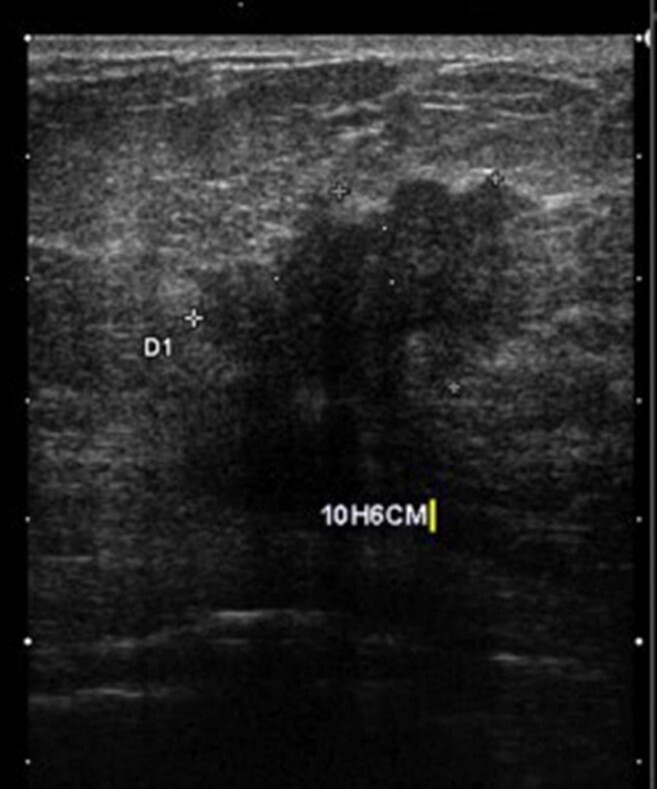

Mammographie du sein G : Échographie du sein G :

Question 10 - Concernant ces résultats, vous notez que (une ou plusieurs réponses exactes) :

Le nodule est hypoéchogène.

Les deux examens sont en faveur d’une lésion maligne.

La mammographie et l’échographie retrouvent un nodule spiculé de 41 mm du quadrant supéro-interne du sein gauche.